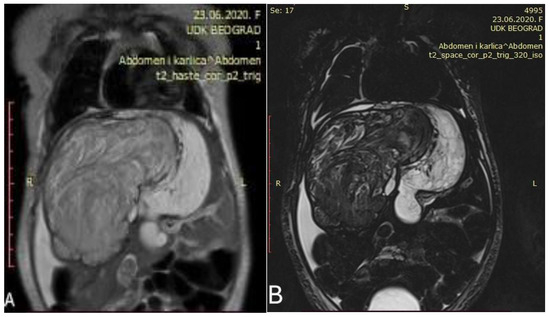

Abdominal MRI revealed a large heterogeneous liver mass that infiltrates most of the right liver (except Couinaud segment VI and VII) and almost the entire left lobe, measuring 120 mm × 85 mm × 78 mm with signs of parenchymal bleeding and necrosis (Figure 2).

Figure 2.

Initial abdominal MRI showed a voluminous heterogeneous tumor occupying the right liver ((A,B) Different coronal slices of the same MRI).